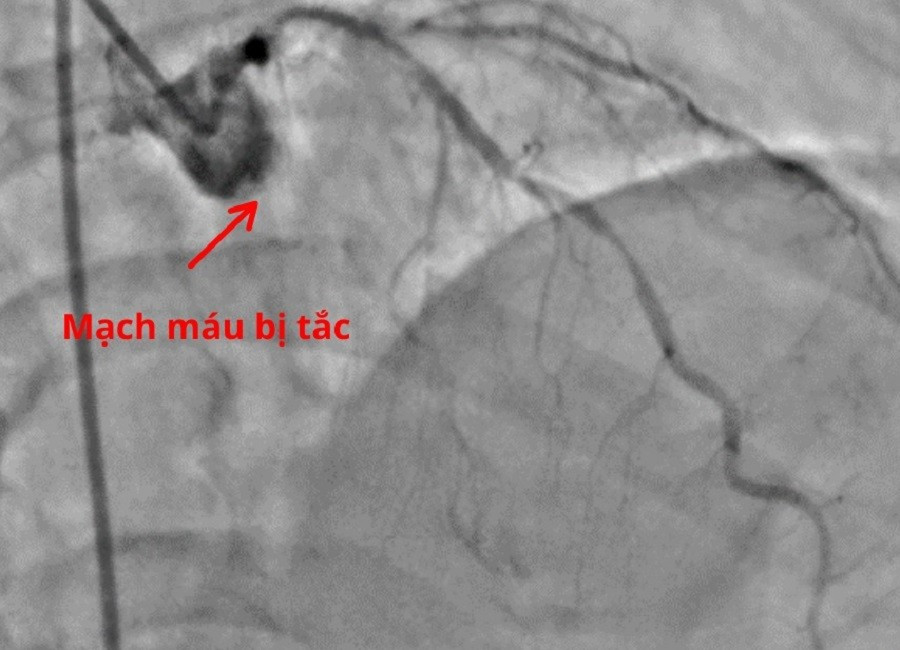

Nhánh mũ động mạch vành bị tắc hoàn toàn là nguyên nhân khiến người bệnh rơi vào nguy kịch

Khi huyết áp được duy trì bằng thuốc vận mạch, ông T. được chuyển thẳng vào phòng Thông tim. Trong quá trình can thiệp, ê kíp bác sĩ phát hiện nhánh động mạch vành mũ của người bệnh bị tắc hoàn toàn. Các bác sĩ tiến hành tái thông mạch vành bằng bóng giúp khôi phục dòng máu nuôi tim mà không cần đặt stent, từ đó giảm nguy cơ tái hẹp về sau.